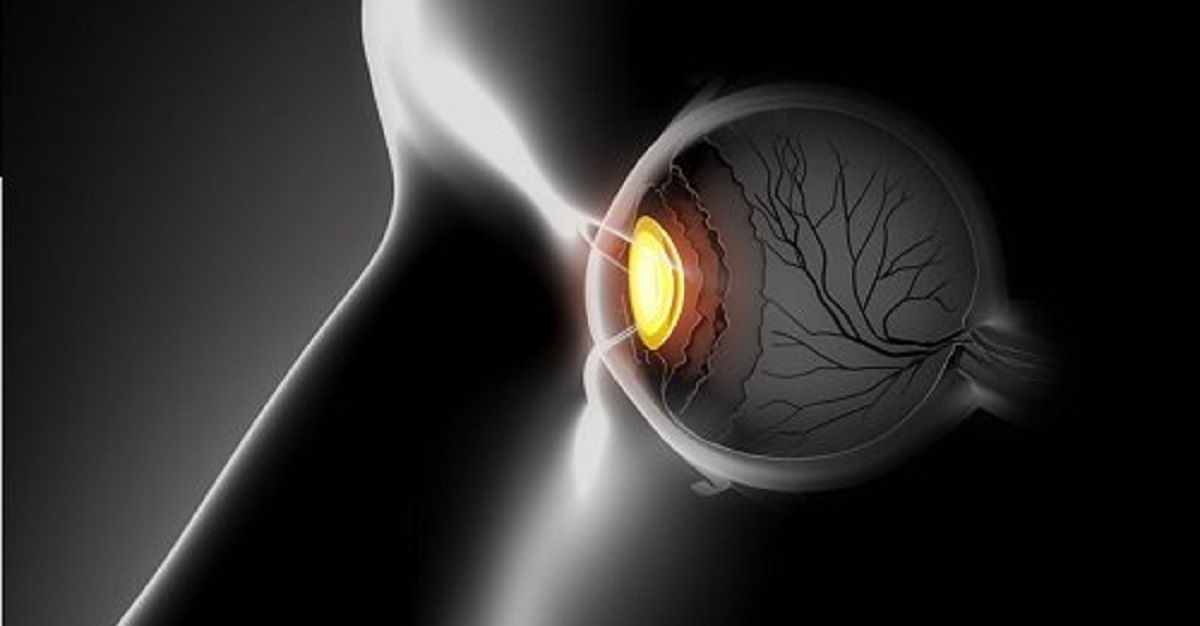

Para mantener la salud de nuestra visión, debemos recibir un aporte determinado de vitaminas y minerales para que el sentido pueda funcionar con normalidad. Hay cosas tan comunes como pasar muchas horas frente al computador, el estrés e incluso algunas dietas extremas provocan que nuestra agudeza visual se vaya deteriorando e incluso podamos desarrollar determinadas enfermedades asociadas a la vista.

También llamada retinol, es una vitamina liposoluble básica para nuestra visión pue estimula la sensibilidad a la luz de la retina. Un déficit de esta vitamina notaremos que en los atardeceres nos costará fijar la vista, nos escocerán los ojos y los sentiremos cansados. Los alimentos que contienen esta vitamina son la zanahoria, leche, espinacas, yema del huevo y mantequilla, entre muchos otros.